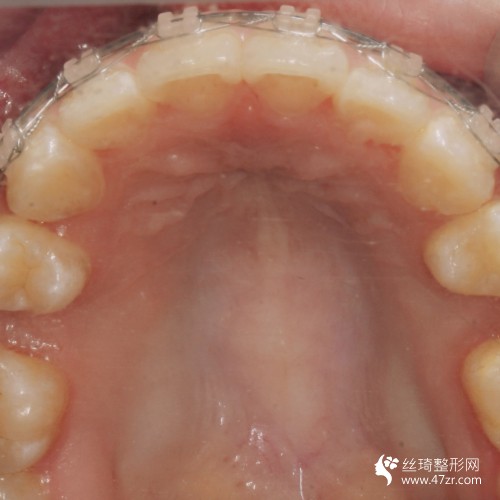

3.手術(shù)案例介紹

術(shù)前:因?yàn)槲业难例X很不好看,所以這種情況給我的外在形象帶來了很大的影響,為了改變我決定到醫(yī)院去做手術(shù),醫(yī)師根據(jù)我的情況給我做了牙齒矯正手術(shù)的方案,看到手術(shù)方案之后,我就決定在昆明美奧口腔醫(yī)院做手術(shù),因?yàn)檫@所醫(yī)院很正規(guī),而且醫(yī)生也是很專業(yè)的,所以我覺得完成手術(shù)之后的果會(huì)很不錯(cuò)。

術(shù)中:在進(jìn)行手術(shù)過程中是比較沒問題沒多少痛感的,因?yàn)獒t(yī)生的手法很輕柔,所以我覺得手術(shù)過程還是比較理想的,醫(yī)生說手術(shù)恢復(fù)起來會(huì)比較慢,讓我聽他的話好好的進(jìn)行護(hù)理。

術(shù)后7天:這幾天一直在聽醫(yī)生的話進(jìn)行很好的護(hù)理,沒有吃堅(jiān)硬的東西,也沒有吃一些太油膩的食物,所以手術(shù)的恢復(fù)還算不錯(cuò)吧,但是這才是剛開始醫(yī)生說要慢慢的去恢復(fù),不要心急,所以我也就只能慢慢的等待了。

術(shù)后90天:很多朋友都說我現(xiàn)在的恢復(fù)是比較不錯(cuò)的,因?yàn)檎w看上去更加好看了,我也覺得是這樣的,雖然手術(shù)還沒有得到完全的恢復(fù),但是可以看出來有了很好的改良。

術(shù)后160天:手術(shù)結(jié)束之后不但使我的牙齒得到了很好的矯正,而且我整個(gè)人的形象也變得更美觀了,所以我對(duì)手術(shù)是感到很滿意的,真的很感謝醫(yī)生,現(xiàn)在手術(shù)的恢復(fù)還沒有完全的恢復(fù)好,所以還是需要進(jìn)行很好的護(hù)理。

術(shù)后365天:手術(shù)恢復(fù)的差不多了,今天到醫(yī)院去復(fù)診的時(shí)候,醫(yī)生說恢復(fù)的很好,在整個(gè)手術(shù)過程中都沒有出現(xiàn)任何不良的情況,真的是太滿意了,很感謝曾強(qiáng)醫(yī)生。